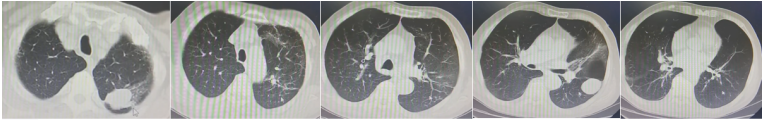

2023年5月26日NGS回报毛霉,经过讨论,建议艾沙康唑、两性霉素B雾化+静脉滴注、奥马环素200 mg ivd首剂,100 mg qd治疗。艾沙康唑200 mg qd+两性霉素B静滴(5月26日两性霉素B胆固醇硫酸酯复合物100 mg qd,5月27日换用两性霉素B脂质体150 mg→250 mg→350 mg qd)+两性霉素B 12.5 mg bid雾化+奥马环素100 mg qd(200 mg ivd首剂)。2023年6月5日复查胸部CT:弥漫性病变明显吸收,左上肺病灶明显呈现机化限制,病灶体积没有扩大;左肺出现新的实变影(图4)。从病灶性质上看,似乎是机化的过程,加之患者临床症状明显改善,经过讨论认为该方案是有效的,所以继续使用该治疗方案。慢性阻塞性肺疾病伴急性加重;肺真菌病(曲霉、毛霉);呼吸衰竭;糖尿病;高血压;低蛋白血症;低钾血症;颈椎术后(脊髓型颈椎病);腰椎间盘突出。①奥玛环素片300 mg/片,每日一次。②两性霉素B每日两次,每次25 mg雾化吸入。2~3月后改每天雾化一次,一次半支(12.5 mg)。③艾沙康唑20 0mg qd,维持30 min。④两性霉素B脂质体350 mg qd 60 min以上滴完。易低钾,注意监测血钾。2023年6月25日出院后复查胸部CT:病灶基本吸收,左下叶出现新病灶,边缘光滑,考虑原有肺大泡内充填了一些渗出性病变(图5)。但并未将其定义为一个新的病变,因为它不像典型的曲霉或毛霉感染的新发病变特征,并且患者症状非常逍遥,所以仍沿用原方案继续治疗。

2023年7月21日胸部CT可见病灶较前进一步吸收(图6),停两性霉素B脂质体,艾沙康唑由静脉序贯为口服,两性霉素B雾化qd。